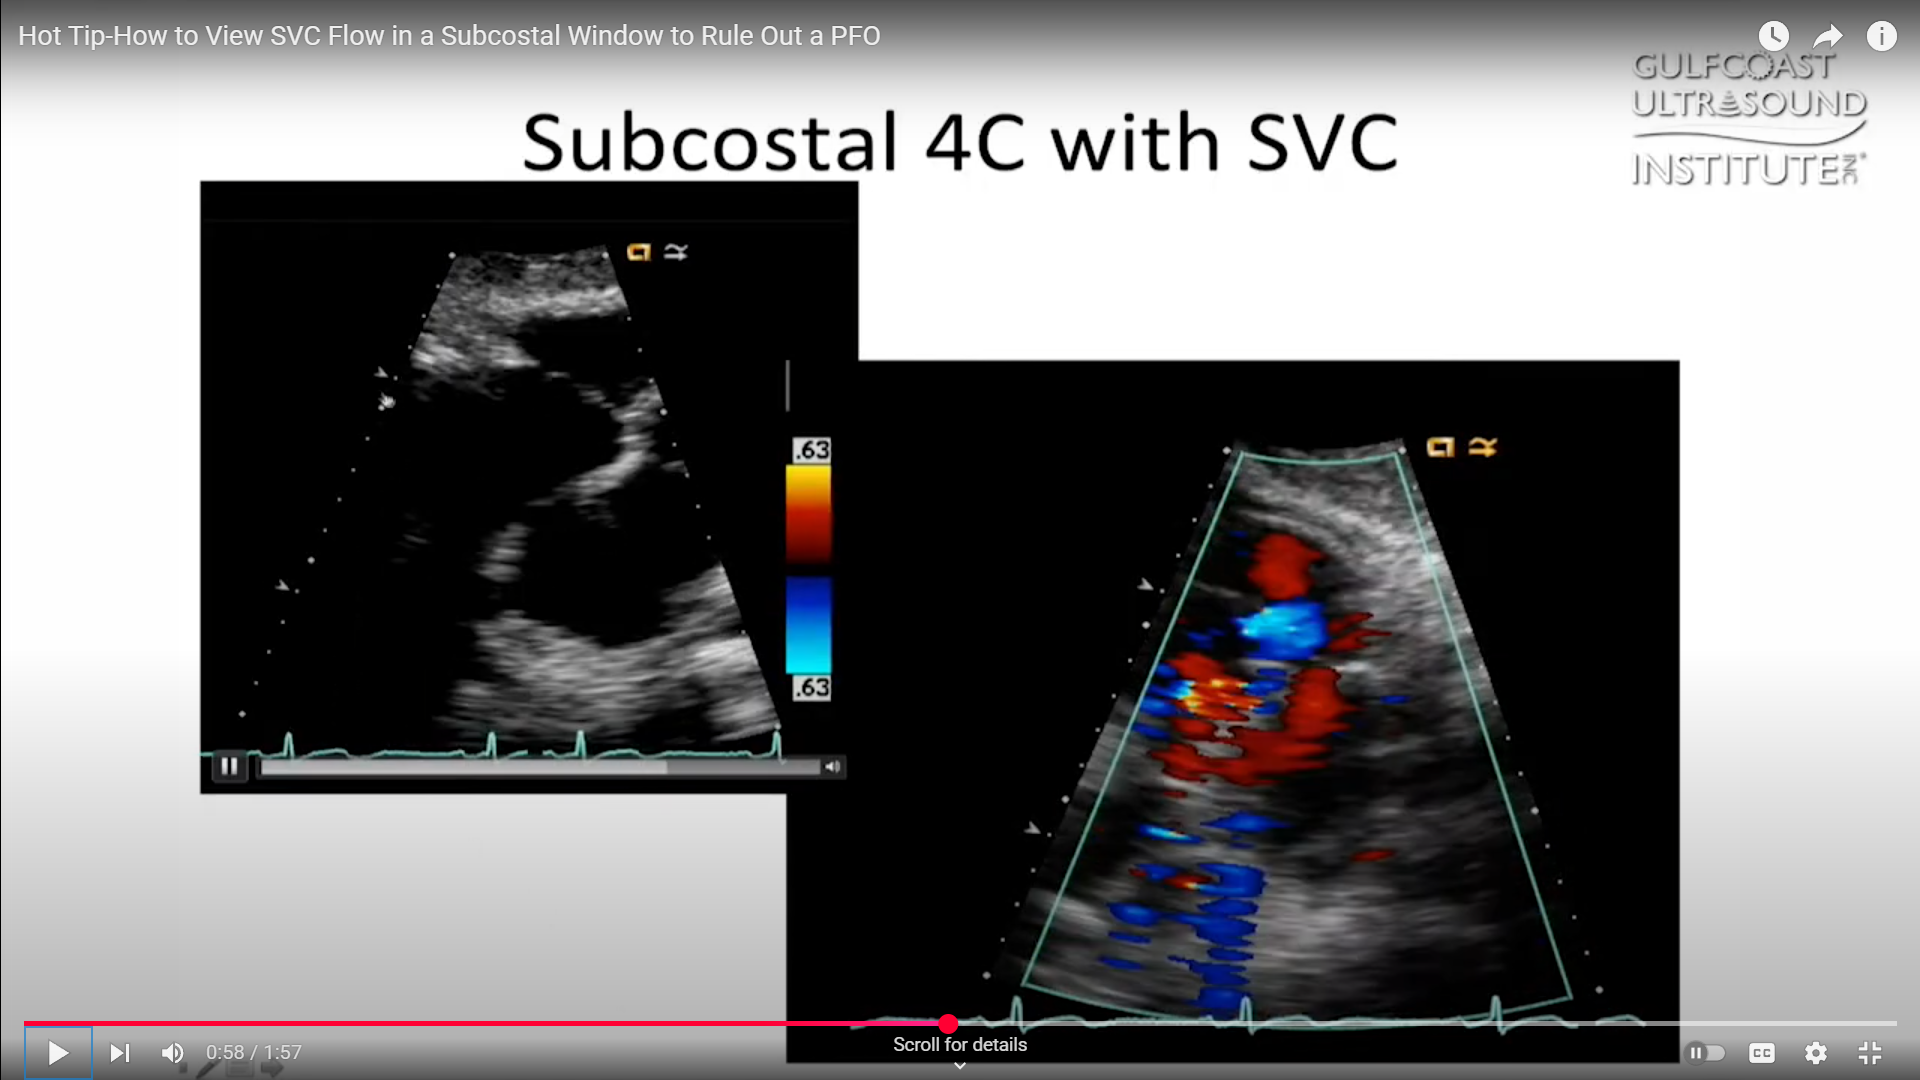

Applying Color Flow Doppler

Once you’ve identified the SVC, applying color flow Doppler can help visualize the blood flow pattern. Normally, you’ll see red laminar flow moving into the right atrium. However, distinguishing between this normal SVC flow and a PFO shunt can be challenging. Sometimes, the color Doppler image isn’t clear enough to show whether there’s a true PFO or just normal flow dynamics.

Here’s where a small adjustment can make a big difference. From your standard three o’clock view of the subcostal window, rotate your probe toward the five o’clock position. By making this shift, you bring the bicaval view into focus, allowing you to see both the inferior vena cava (IVC) and SVC together. On your screen, you’ll notice the SVC flow coming up and curving slightly to the right.

In this view, you’ll often be able to see the small PFO flow separate from the normal SVC flow. On a still frame, the SVC flow should appear as a consistent laminar pattern, while the PFO flow will be visible as a distinct jet at the level of the fossa ovalis. This adjustment provides a clearer way to differentiate between these two important findings.